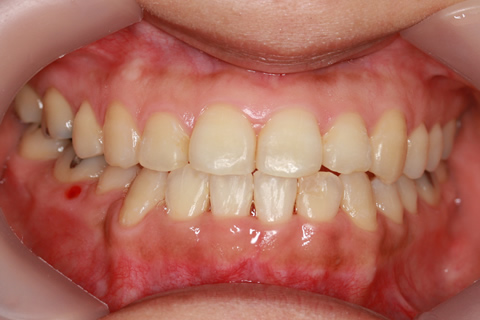

受け口(反対咬合)の症例

症例一覧